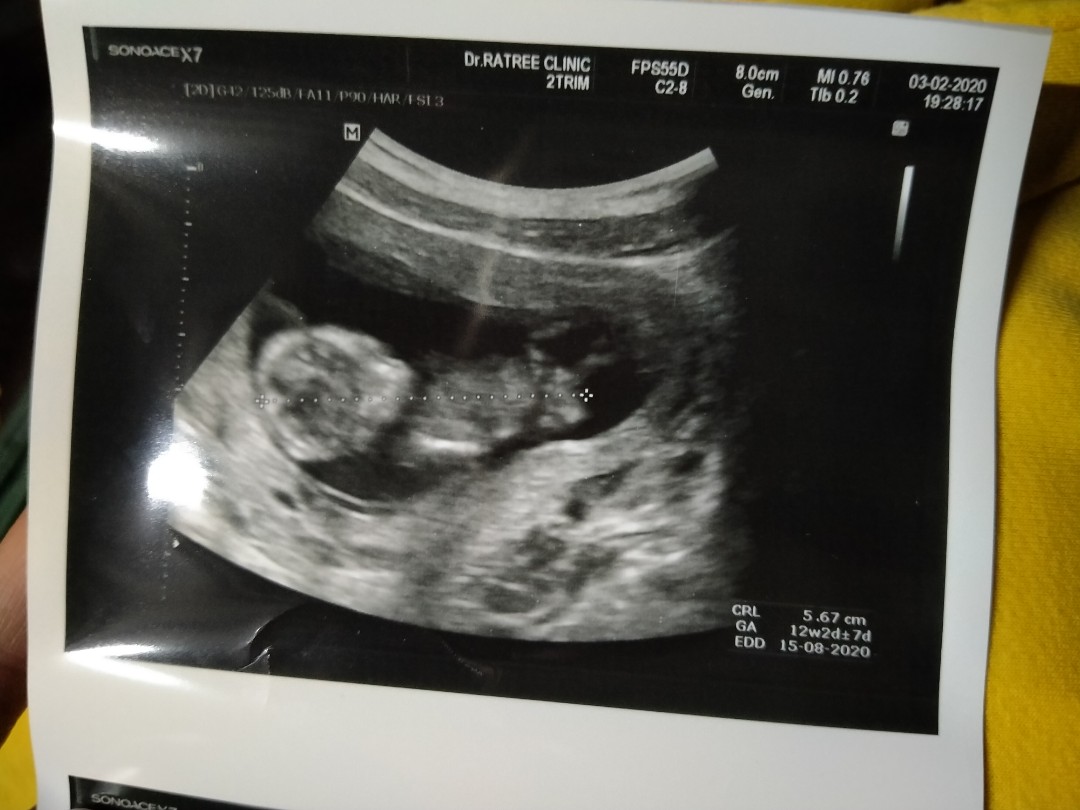

12w